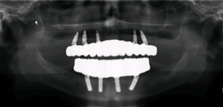

Fig 6. Placement of tilted

implants in existing native bone enables expedited therapy in the case of terminal dentitions.

Fig 5: Representative scenario involving advanced generalized periodontitis with marked bone

loss. Immediate placement (and loading) requires primary stability that cannot be achieved in the

residual tooth sockets of such cases. Alveolectomy and tilted implant placement in the residual

native bone is one approach to immediate implant therapy. In such cases, there is often insufficient

bone volume in zone 3 for implant placement. Fig 6: Panoramic radiographic evaluation following

final prosthesis delivery illustrates the use of tilted implants in zone 2, which was required

to achieve anterior-posterior distribution of implants to support molar function and permit the

intervening period of immediate provisionalization.

Figure 6